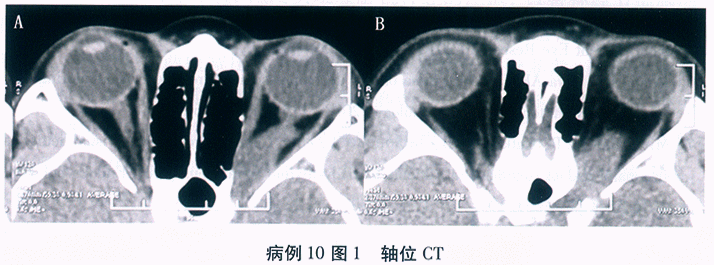

问题 1176

患者,男性, 28岁,主诉“双眼先后眼红、畏光、流泪、异物感9天, 左眼视力下降2天”。患者半月前曾至公共浴室洗浴,其后出现左眼红, 流泪,异物感等症状, 无明显分泌物,2天后右眼亦出现同样症状, 去医院就诊为“急性结膜炎”,予以局部抗病毒、抗生素滴眼液治疗, 但病情进一步发展,而且左眼出现视力下降, 遂至我院就诊。